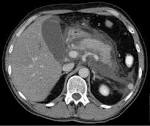

Pankreatitis Eine akute Pankreatitis zeigt sich durch heftigen Schmerz im Oberbauch, belkeit, Erbrechen, Verstopfung und Fieber. 2-Heptyl-3-hydroxy-4-quinolone, known as the Pseudomonas Quinolone Signal, is a key regulator of bacterial cooperative behaviour known as quorum sensing. 2007: Schwerter des Königs Dungeon Siege (In the Name of the King : A).

Pankreatitis